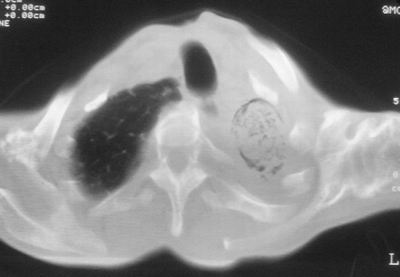

患者,男,47岁,反复咳嗽、咯痰、咯血3年,再发5天。痰培养未找到真菌、抗酸杆菌、癌细胞。

以下是引用xulianj在2008-2-25 21:01:00的发言:[br]左肺上叶结核伴肺纤维化有霉菌球形成,纵隔移位,左肺下叶感染性病变,建议抗炎抗结核后复查,双肺气肿.

考虑:左肺慢纤伴霉菌球形成、双肺全小叶型肺气肿。

1)考虑为:左肺上叶肺结核(空洞形成),伴左下肺感染;不排除霉菌感染可能。2)肺气肿。

左肺上叶结核伴肺纤维化空洞形成并左肺下叶感染,纵隔牵拉移位,建议作进一步检查排除左侧肺霉菌感染可能。